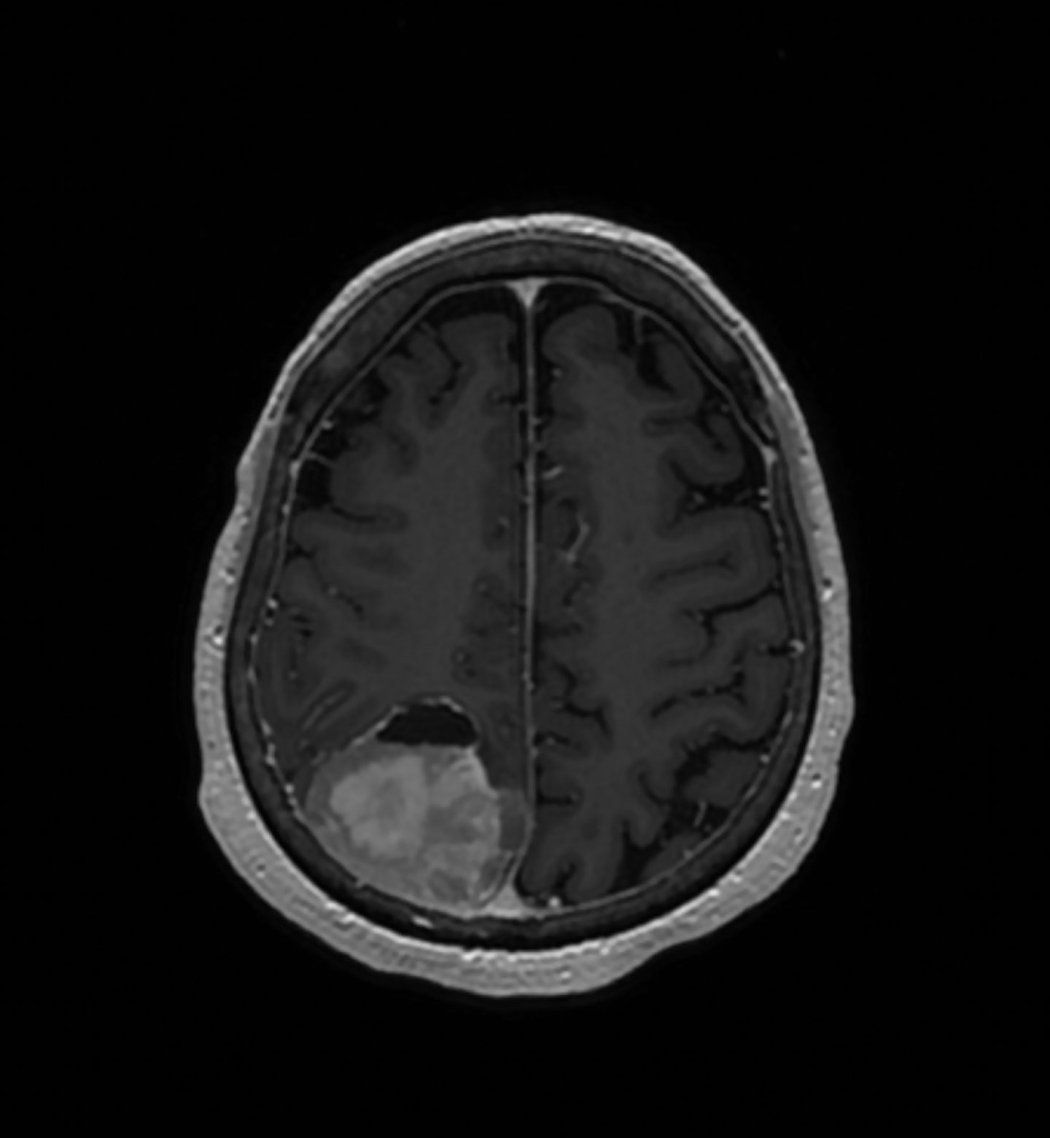

Screening tumors using this new approach could change the course of treatment for nearly 1 in 3 people with meningioma, the most common form of brain tumor diagnosed in 42,000 Americans each year. Unlike other brain tumors, meningiomas occur most often in female, Black and elderly patients.

Because meningiomas grow slowly, a patient may be unaware of their tumor until they start to experience neurological symptoms like numbness, vision loss or personality changes. There are no pharmaceutical treatments, so doctors rely on surgery to remove the tumor and radiation to prevent it from growing back. Doctors treat these tumors based on guidance from the World Health Organization, which stages them according to severity.

Pathologists currently classify meningiomas by looking at them under a microscope for features that indicate whether they may grow back, a system that is very good but not perfect. Patients with Grade 1 tumors don’t usually receive radiation treatment if their tumors can be removed completely during surgery. Yet approximately 20% of the time, the tumors recur. Those with Grade 2 and 3 tumors, which are much more aggressive and more likely to grow back after surgery, are often treated with radiation after surgery. It has been unclear how many of these patients, particularly those with Grade 2 tumors, actually need radiation treatment.